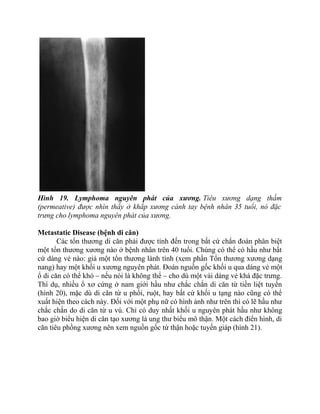

Hình 21. Ung thư biểu mô tế bào thận di căn. Một tổn thương tiêu xương ở thân

xương đùi, nó điển hình cho di căn từ ung thư biểu mô tế bào thận. Có đến 1/3 các

ung thư biểu mô tế bào thận biểu hiện ban đầu bằng di căn xương. Ung thư biểu

mô tế bào thận hầu như không bao giờ biểu hiện là ổ di căn tạo xương.